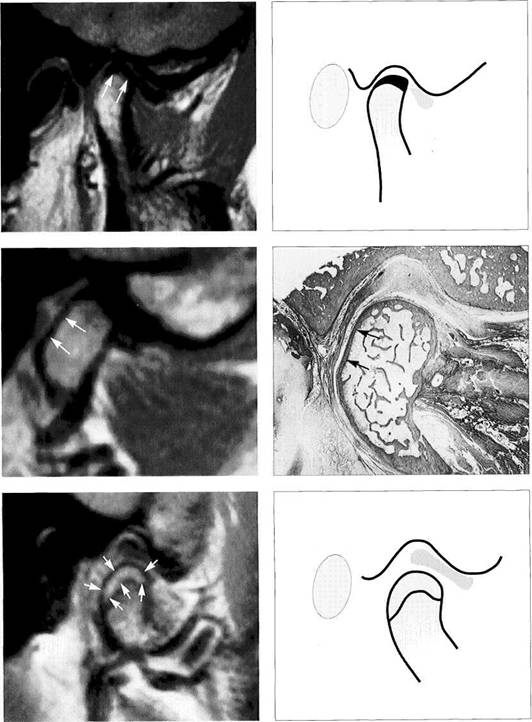

Disk Position in the Frontal Plane

The lateral and medial portions of the joint are evaluated in an MR image made in the frontal plane with the jaws closed (Brooks and Westesson 1993). Angling the frontal plane so that it is parallel with the long axis of the targeted condyle will improve the quality of the image (Westesson 1993). The position of the disk should be determined by using a slice through the pars posterior because the other parts of the disk cannot be as well depicted due to their thinness. When healthy subjects were studied, 1.8% were found to have disks displaced laterally, and 0.9% medially. Among tem­poromandibular joint patients the incidence rose to 4.5% for

lateral and 4.1% for medial disk displacements (Tasaki and Westesson 1993). A macroscopic study of anatomical speci­mens found similar values (3% lateral, 5% medial; Chris­tiansen and Thompson 1990). Incorrect angulation of the frontal plane can give a false picture of a lateral displace­ment (angulation too small) or medial displacement (angu­lation too large) of the disk and thereby lead to an incorrect interpretation and a different set of percentage figures (Khoury and Dolan 1986, Katzberg et al. 1988, Schwaighofer et al. 1990, Hugger et al. 1993).

Physiological disk position

Left: Schematic drawing illustrating normal disk position in the frontal plane.

Right: MRI of the right temporo­mandibular joint of a 24-year-old man. The frontal plane is angled so that it is parallel with the long axis of the condyle. With the jaws closed, the pars posterior of the disk is centered over the condyle.

Medial disk displacement

Left: Schematic drawing of a medial disk displacement in the frontal plane.

Right: MRI of the right temporo­mandibular joint of a 24-year-old patient. An adequate diagnosis of lateral and medial disk displace­ments cannot be made with arthrography and arthrotomogra-phy alone (Kurita et al. 1992a,b).

Lateral disk displacement

Left: Schematic drawing of a lateral disk displacement in the frontal plane.

Right: MRI of the right temporo­mandibular joint of a 23-year-old woman who sustained a fracture of the neck of the condyle at age 14 years. The condyle was tipped medially and has healed in an ab­normal position. The lateral disk displacement is causing pain and recurring limitation of jaw opening.